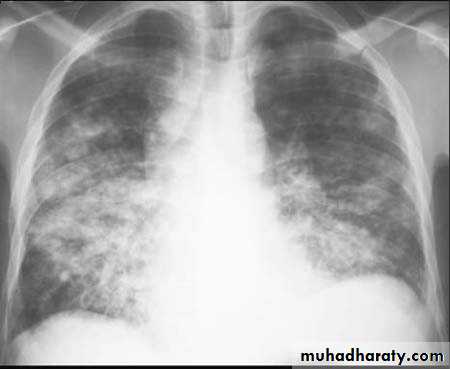

Bronchopneumonia

Bronchopneumonia (also sometimes known as lobular pneumonia 1) is a radiological pattern associated with suppurative peribronchiolar inflammation and subsequent patchy consolidation of one or more secondary lobules of a lung in response to a bacterial pneumonia.Broncho pneumonia

Multi-focal consolidation

Multiple areas of opacity seen throughout the lung most often is due to bronchopneumonia, starting from bronchi and spreading outwards. Usually ill defined with peripheral distribution. Neoplasms such as a primary malignancy or metastasis can also cause this picture.